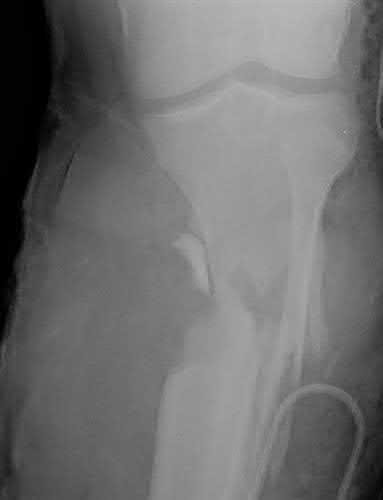

Figures A-C are the radiographs of a 26-year-old male who presents to the emergency department following a motocross accident. Two attempts at a closed reduction by the on-call orthopedic resident were unsuccessful. Figures D and E are the pre-operative axial CT-images that were obtained. The patient undergoes surgical fixation seen in Figure F. Limitations in post-operative dorsiflexion is likely influenced by which of the following?

The rare Bosworth fracture-dislocation is a posterior dislocation of the fibula which becomes entrapped behind the tibia. As demonstrated in this vignette, these injuries are extremely difficult to close reduce secondary to the ridge of the posterolateral distal tibia. The irreducible nature of this injury is a known risk factor for the development of compartment syndrome. The CT images further demonstrate fracture extension to the posteromedial rim (“posterior pilon variant”). In this situation, the only effective method to reduce the fracture is through an open posterolateral approach with the interval between the flexor hallucis longus and the peroneal tendons. This is the same approach that is utilized for fixation of the posterolateral fragment and fibula. Loss of dorsiflexion has been demonstrated following this fracture pattern with posterior fixation. The positioning of the plates in Figure F suggests the

utilization of a posterolateral approach.

Figures A-C: The initial radiographs reveal the posterior subluxation of the talus with associated posterior subluxation of the fibula without significant coronal plane deformity. This deformity should raise the suspicion of a Bosworth fracture-dislocation, especially if closed reduction is not successful. Figures D and E: Axial CT images demonstrating Bosworth fracture-dislocation of the fibula entrapped behind the tibia. Also, note the fracture extension to the posteromedial rim in this posterior pilon variant.

Figure F: Positioning of the plate suggests a posterolateral approach to address both the fibula and posterior malleolus fractures.